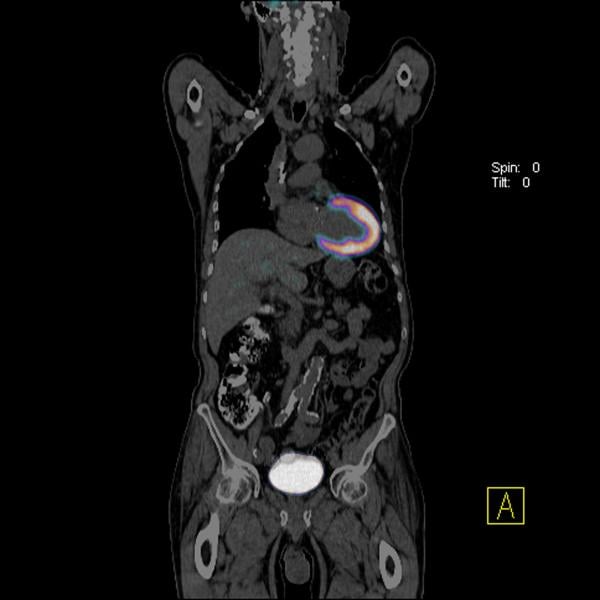

PET Scans & Imaging 101 Imaging Technology News

Mediphany How to read an MRI or CT scan

Abdominal CT scan Information